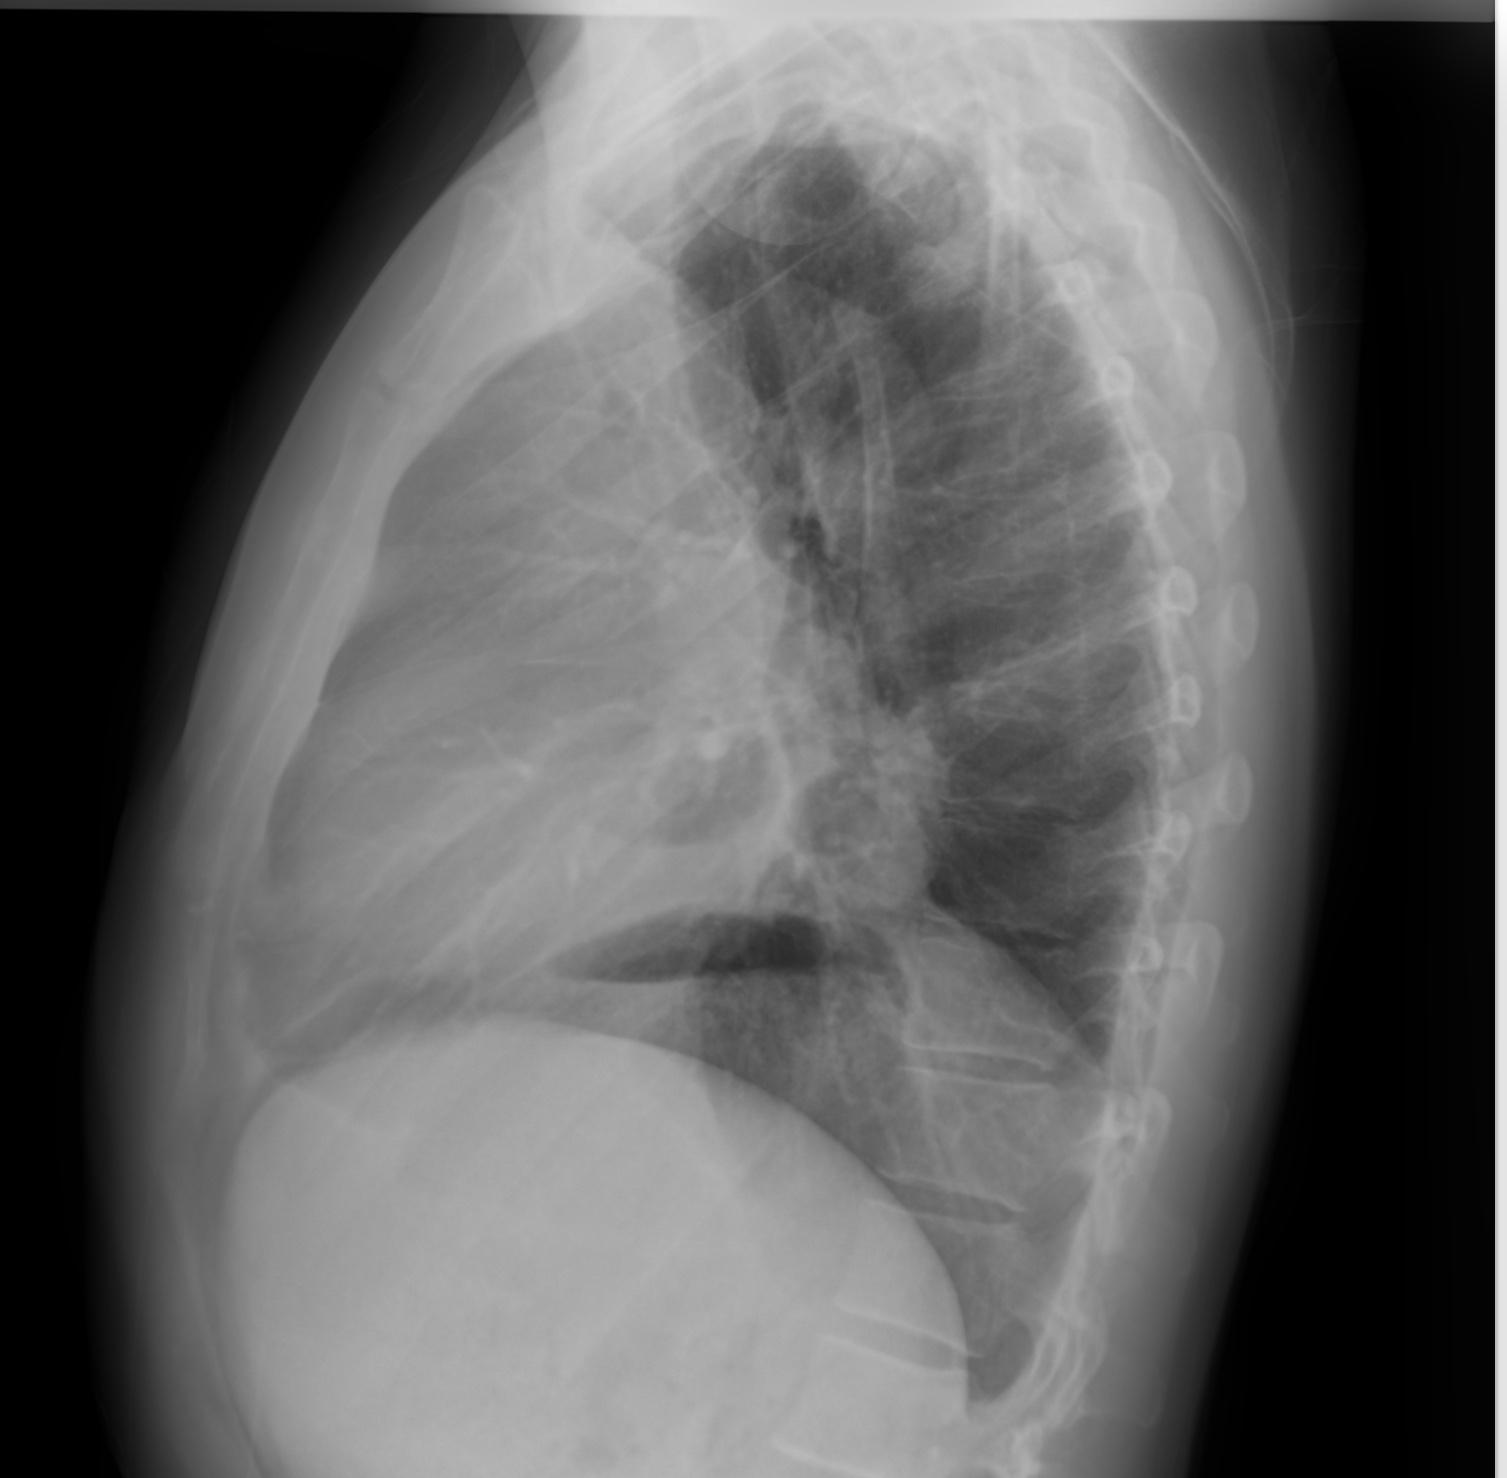

图2 侧位片证实肿块位于前纵隔,胸骨后间隙占位

后前位胸片显示左肺周围病变,伴有对侧气管移位和心缘剪影征阴性,同时由于对侧肺代偿性过度充气导致左半膈肌升高。侧面投影显示胸骨后间隙占位,并伴“脊柱征”。增强CT显示先前识别的病变表现不均匀性,主要呈现周边强化,以及中央低密度区域,可能表明有坏死。其位于前纵隔内,不浸润邻近组织,但支气管血管结构向对侧移位。此外,可以观察到右肺动脉受压,同时存在胸腔积液